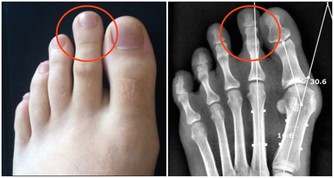

6、關節攣縮:腦梗塞病人如果沒有得到良好的康復訓練,患側的肌肉會發生廢用性萎縮,在肌肉萎縮和張力升高的共同作用下,關節長期不能正常活動,會造成病人關節畸形、攣縮。患處的關節活動會變得很疼痛。